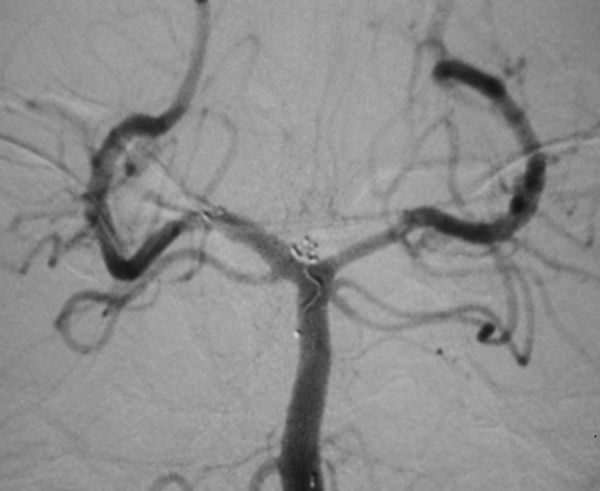

病例3、巨大动脉瘤栓塞:女性,66岁。左侧后交通巨大宽颈动脉瘤破裂出血,动脉瘤大小约7X8X10mm,患者意识模糊,脑肿胀明显,脑压极高,手术夹闭困难,为了防止动脉瘤再次破裂出血危及生命,孟祥靖主任带领全科医生经过仔细分析,决定采用支架辅助+弹簧圈栓塞的方法处理动脉瘤,3月20日孟祥靖主任、郭建主治医师在介入科、麻醉科的密切配合下,动脉瘤完全闭塞,目前,患者一般情况好,正在逐步康复中。

病例3:后交通巨大动脉瘤栓塞术前、后